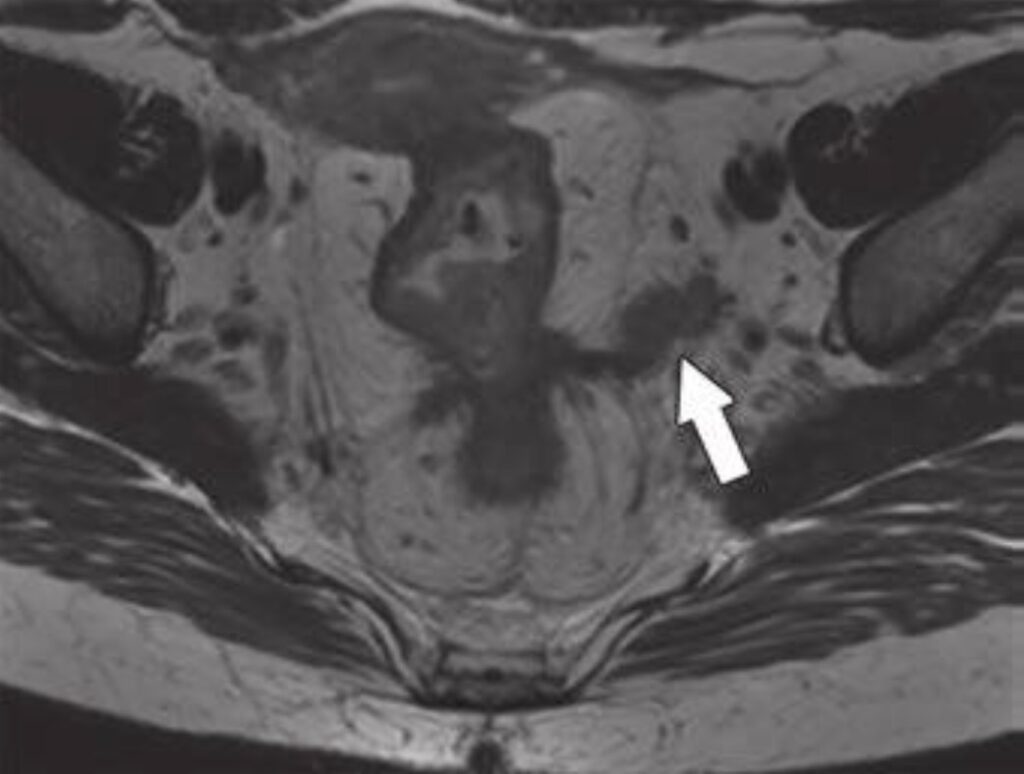

Fig. 1—59-year-old patient with rectal cancer with extramesorectal

vessel involvement, consistent with T category of T4b. Axial (top) and

axial oblique (bottom) T2-weighted images show rectal tumor that extends

through extramesorectal vein (arrow), which according to expert opinion

warrants classification as T4b.